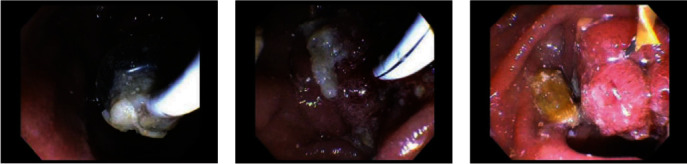

The patient underwent an outpatient ERCP with the successful removal of large amounts of food material, sludge, and white stones from the bile duct using a 15 mm balloon (Figures 2 and 3). During ERCP, the prior sphincterotomy was noted to be stenosed and a biliary sphincterotomy was performed. There was no duodenal diverticulum seen during ERCP. No further imaging such as endoscopic ultrasound or magnetic resonance cholangiopancreatography (MRCP) was obtained prior to ERCP due to the likely culprit of debris in the CBD stump seen on CT imaging, and the dual benefit of imaging and treatment that ERCP affords.